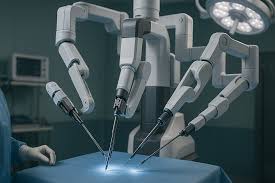

Introduction to Robotic Assisted Surgery Robotic assisted surgery in Korba …

Introduction to Robotic Orthopedic Surgery Robotic orthopedic surgery in Korba …

Introduction to Robotic Assisted Surgery Robotic assisted surgery in Khairagarh-Chhuikhadan-Gandai …

Introduction to Robotic Orthopedic Surgery Robotic orthopedic surgery in Khairagarh-Chhuikhadan-Gandai …